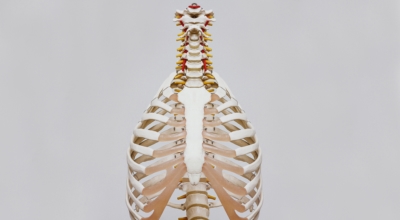

갈비뼈란?

흉추와 복장뼈를 연결해서 가슴 전체를 둘러싸고 있는 가슴우리(흉강)을 형성하는 긴 곡선의 뼈를 말해요. 갈비뼈는 폐, 심장 등 내부 가슴 장기들을 지켜주고 가슴우리의 팽창과 수축으로 호흡을 도와주어요. 우리 몸은 총 12쌍의 갈비뼈를 갖고 있어요. 1~7번 갈비뼈는 복장뼈와 직접 관절로 연결되어 있어 참갈비뼈라고 하며, 8~12번 갈비뼈는 거짓 갈비뼈라고 하는데 거짓 갈비뼈 중 8, 9, 10번 갈비뼈는 하나의 연골을 통해 복장뼈와 연결되어 있고 나머지 11~12번째 갈비뼈는 뜬갈비뼈로 복장뼈와 연결되어 있지 않아요.